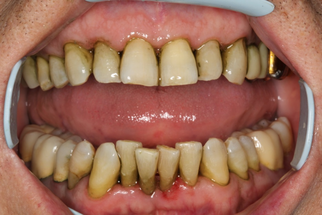

В основной группе 3 проводили фотодинамическую терапию с помощью препарата «Гелеофор» и светодиодного аппарата АФС «Спектр». По сравнению с традиционной антимикробной терапией с применением геля «Метрогил-Дента», противовоспалительный эффект которой наблюдался лишь после завершения всего курса лечения, пациенты группы 3 почувствовали улучшение своего состояния непосредственно на стоматологическом приеме после проведения фотодинамической терапии. После первого сеанса 24,0% пациентов отмечали снижение дискомфорта и болевых ощущений в полости рта, на которые жаловались до лечения. После второго сеанса ФДТ уже 62,0% пациентов субъективное улучшение. После третьего сеанса практически все пациенты (92,0%) отмечали улучшение состояния пародонта, снижение кровоточивости при чистке зубов, уменьшение воспаления десны и болевых ощущений. Улучшение состояния тканей пародонта подтверждалось и при объективном обследовании полости рта (Рисунок 14).

| Клиническая картина до лечения | Ортопантомограмма до лечения |

| Проведена профессиональная гигиена | Обработка ПК гелем «Гелеофор» |

| Активация фотосенсибилизатора | Состояние после первого сеанса ФДТ |

| Состояние после второго сеанса ФДТ | Состояние после третьего сеанса ФДТ |

| Рисунок 14. Динамика состояния тканей пародонта у пациента с ХГП тяжелой степени группы 3 в ходе проведения курса фотодинамической терапии. | |